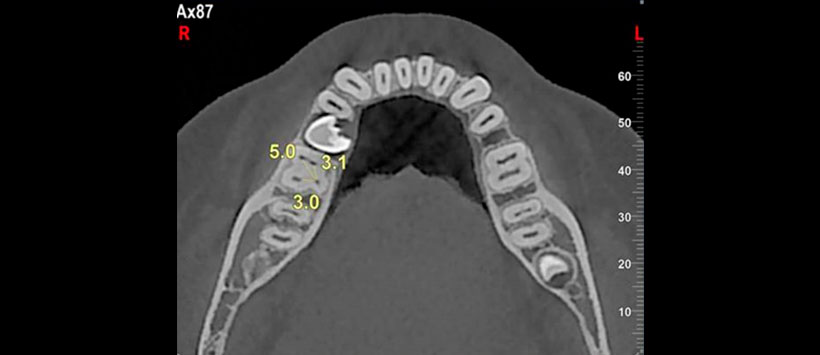

Los primeros y segundos dientes molares mandibulares de 850 pacientes turcos se evaluaron mediante tomografía computarizada de haz cónico. Se examinaron un total de 2800 primeros molares mandibulares y segundos molares. El examen CBCT se realizó a cinco niveles axiales diferentes. Se midió la prevalencia de la distribución de radix entomolaris total, unilateral-bilateral, derecha-izquierda y de género, y la clasificación de las configuraciones del canal de radix entomolaris.

Radix entomolaris se encontró en 2.9% (n = 25) de los pacientes y 1.2% (n = 34) de los dientes. La prevalencia de radix entomolaris en los primeros molares mandibulares fue mayor que en los segundos molares mandibulares (p <0.01), en hombres que en mujeres (p <0.05) y en el lado derecho que en el lado izquierdo. Se encontró un tubérculo adicional en el 23% de los dientes con radix entomolaris. Para la orientación bucolingual, la variación del canal tipo A fue la más alta y la variación del canal tipo C fue la más baja. En cuanto a la ubicación de las partes cervicales, la variación del canal tipo III fue la más alta, mientras que la variación del canal tipo I fue la más baja.